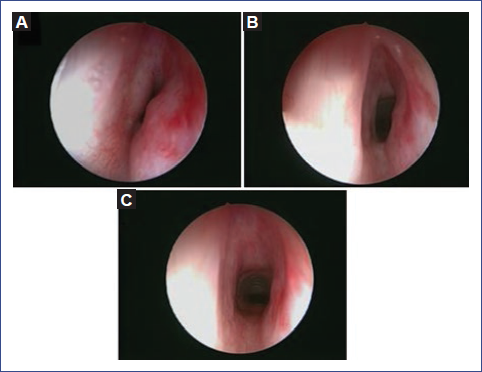

El tiempo observado desde el inicio de la terapia hasta la documentación macroscópica de una reducción mayor del 50% del tamaño de la lesión fue de una media de 8.4 semanas, con un rango de 2 semanas a 6 meses (Fig. 1). Tres de los pacientes tenían estigmas externos de hemangioma; uno de ellos solo en el labio inferior, uno en la región parotídea izquierda y otro en el mentón. Todas las lesiones externas disminuyeron rápidamente de intensidad, aunque persistieron por un tiempo variable y desaparecieron al cabo de 1 a 2 meses de tratamiento (Fig. 2).

Figura 1 Efectos secuenciales del tratamiento con propranolol en el caso 2. A: lesión confinada al espacio subglótico, originada en ambas paredes laterales, que obstruye el 90% de la luz respiratoria. B: imagen endoscópica en el día 10 del tratamiento, con una reducción importante del volumen tumoral, que evidencia una resolución completa del componente izquierdo de la lesión. C: resolución completa a los 6 meses de tratamiento.